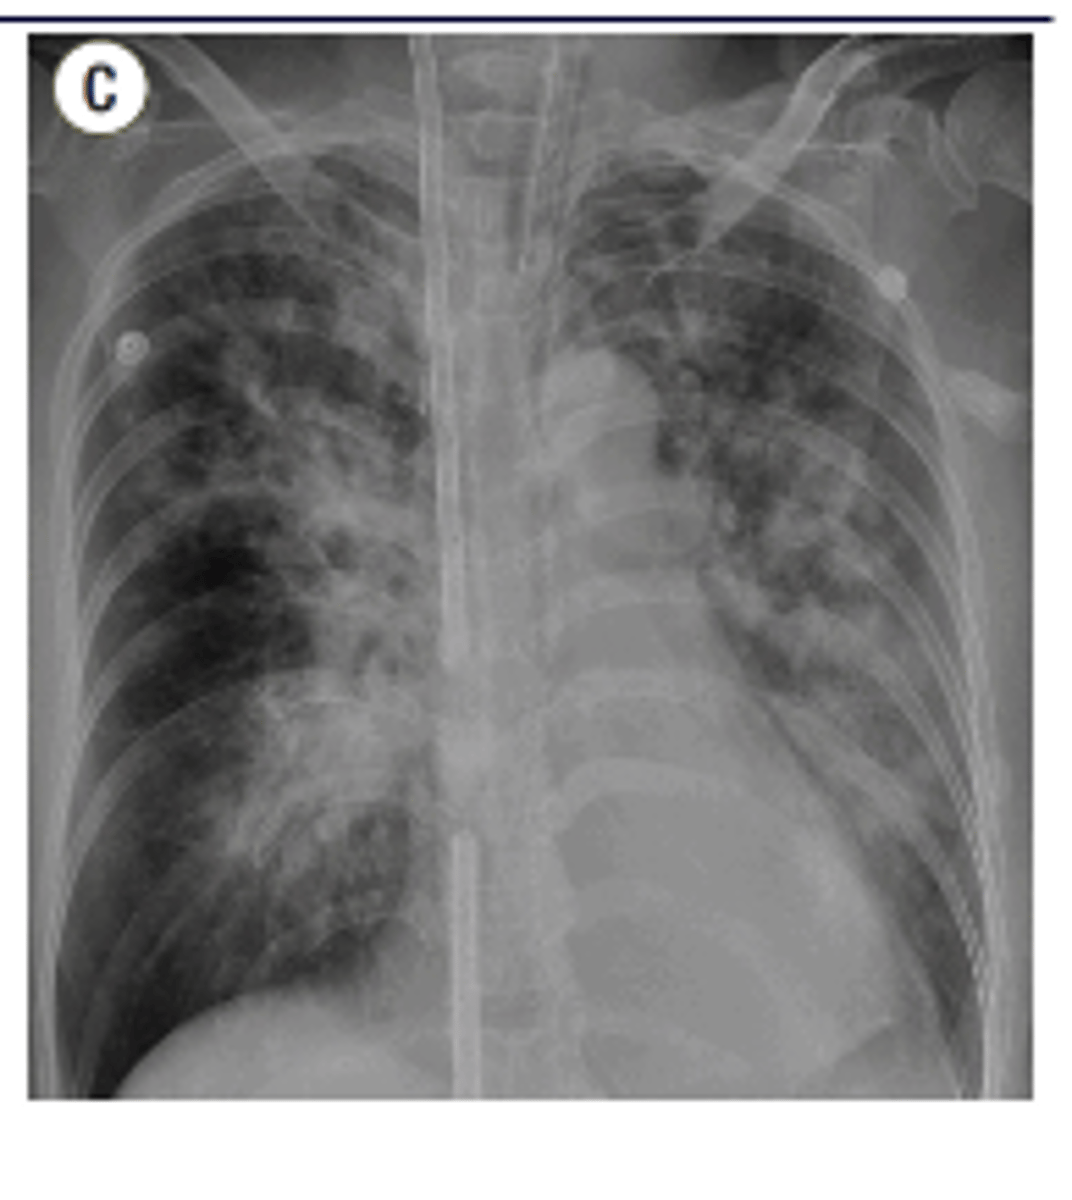

ARDS x-ray appearance

"white out appearance" sometimes with sparing of costophrenic angles

<p>"white out appearance" sometimes with sparing of costophrenic angles</p>